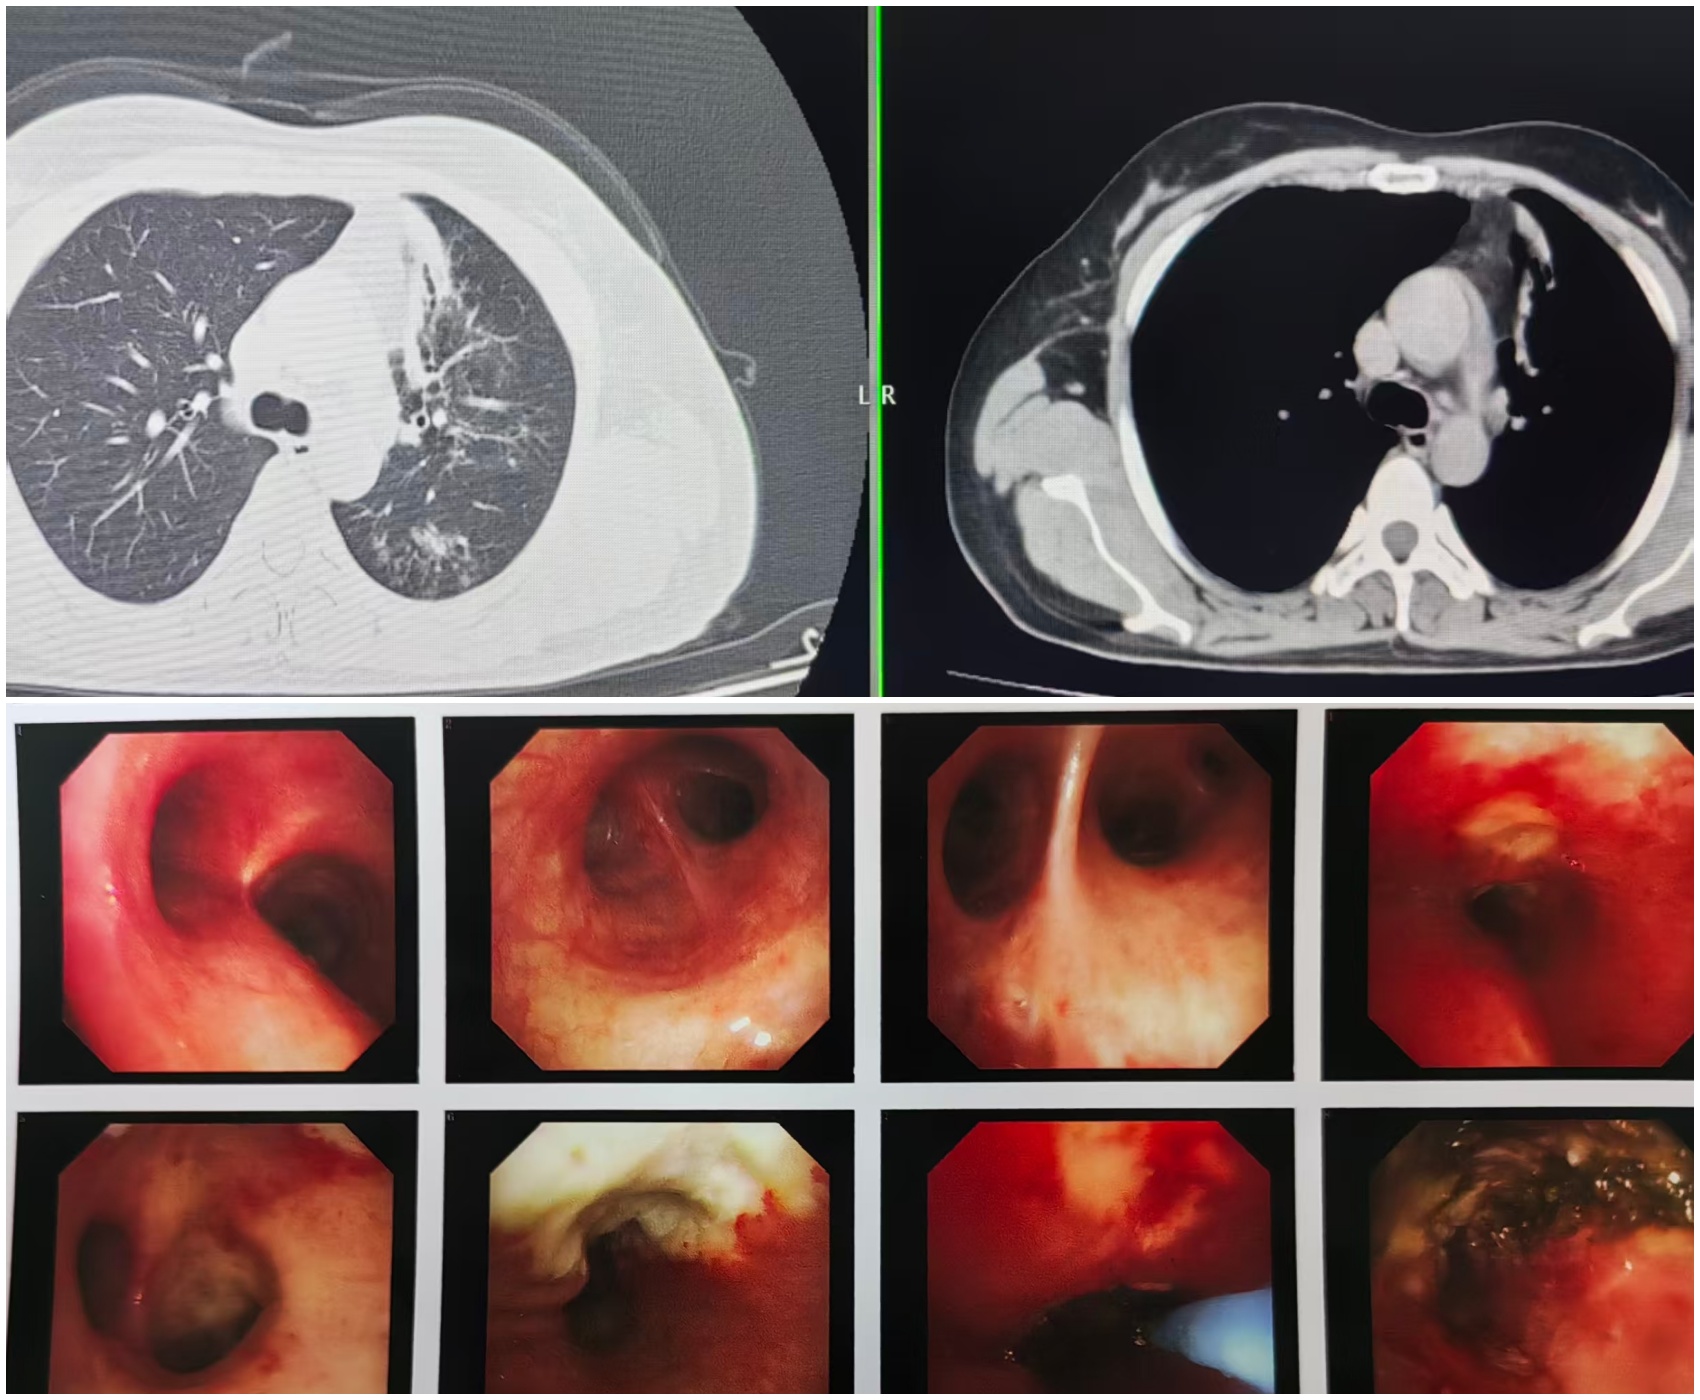

患者王女士(化名)的“呼吸之路”布满坎坷。她曾确诊肺结核,因未接受规范治疗,病情迁延不愈。近一年来,反复咳嗽成为她的 “心头患”,尤其在接触烟味后,咳嗽症状会即刻加重。半月前,王女士咳嗽、咳痰症状突然加剧,还伴随胸痛不适,遂紧急前往我院就诊。检查结果令人揪心:胸部 CT 提示左肺多发性病变,进一步的气管镜检查显示,其左肺上叶支气管已被大量干酪样坏死物完全堵塞,肺叶面临完全坍塌的危机,若不及时干预,肺功能将遭受永久性损伤。

手术当日,在麻醉与围术期医学科团队的紧密配合下,呼吸内镜团队精准操作,将支气管镜顺利送达病灶部位。医生利用氩气刀技术,对堵塞气道的干酪样坏死物进行逐层、精准消融,成功打通堵塞的支气管管腔。整个手术过程行云流水,出血量极少,患者生命体征平稳,术后安返病房,目前恢复状况良好。